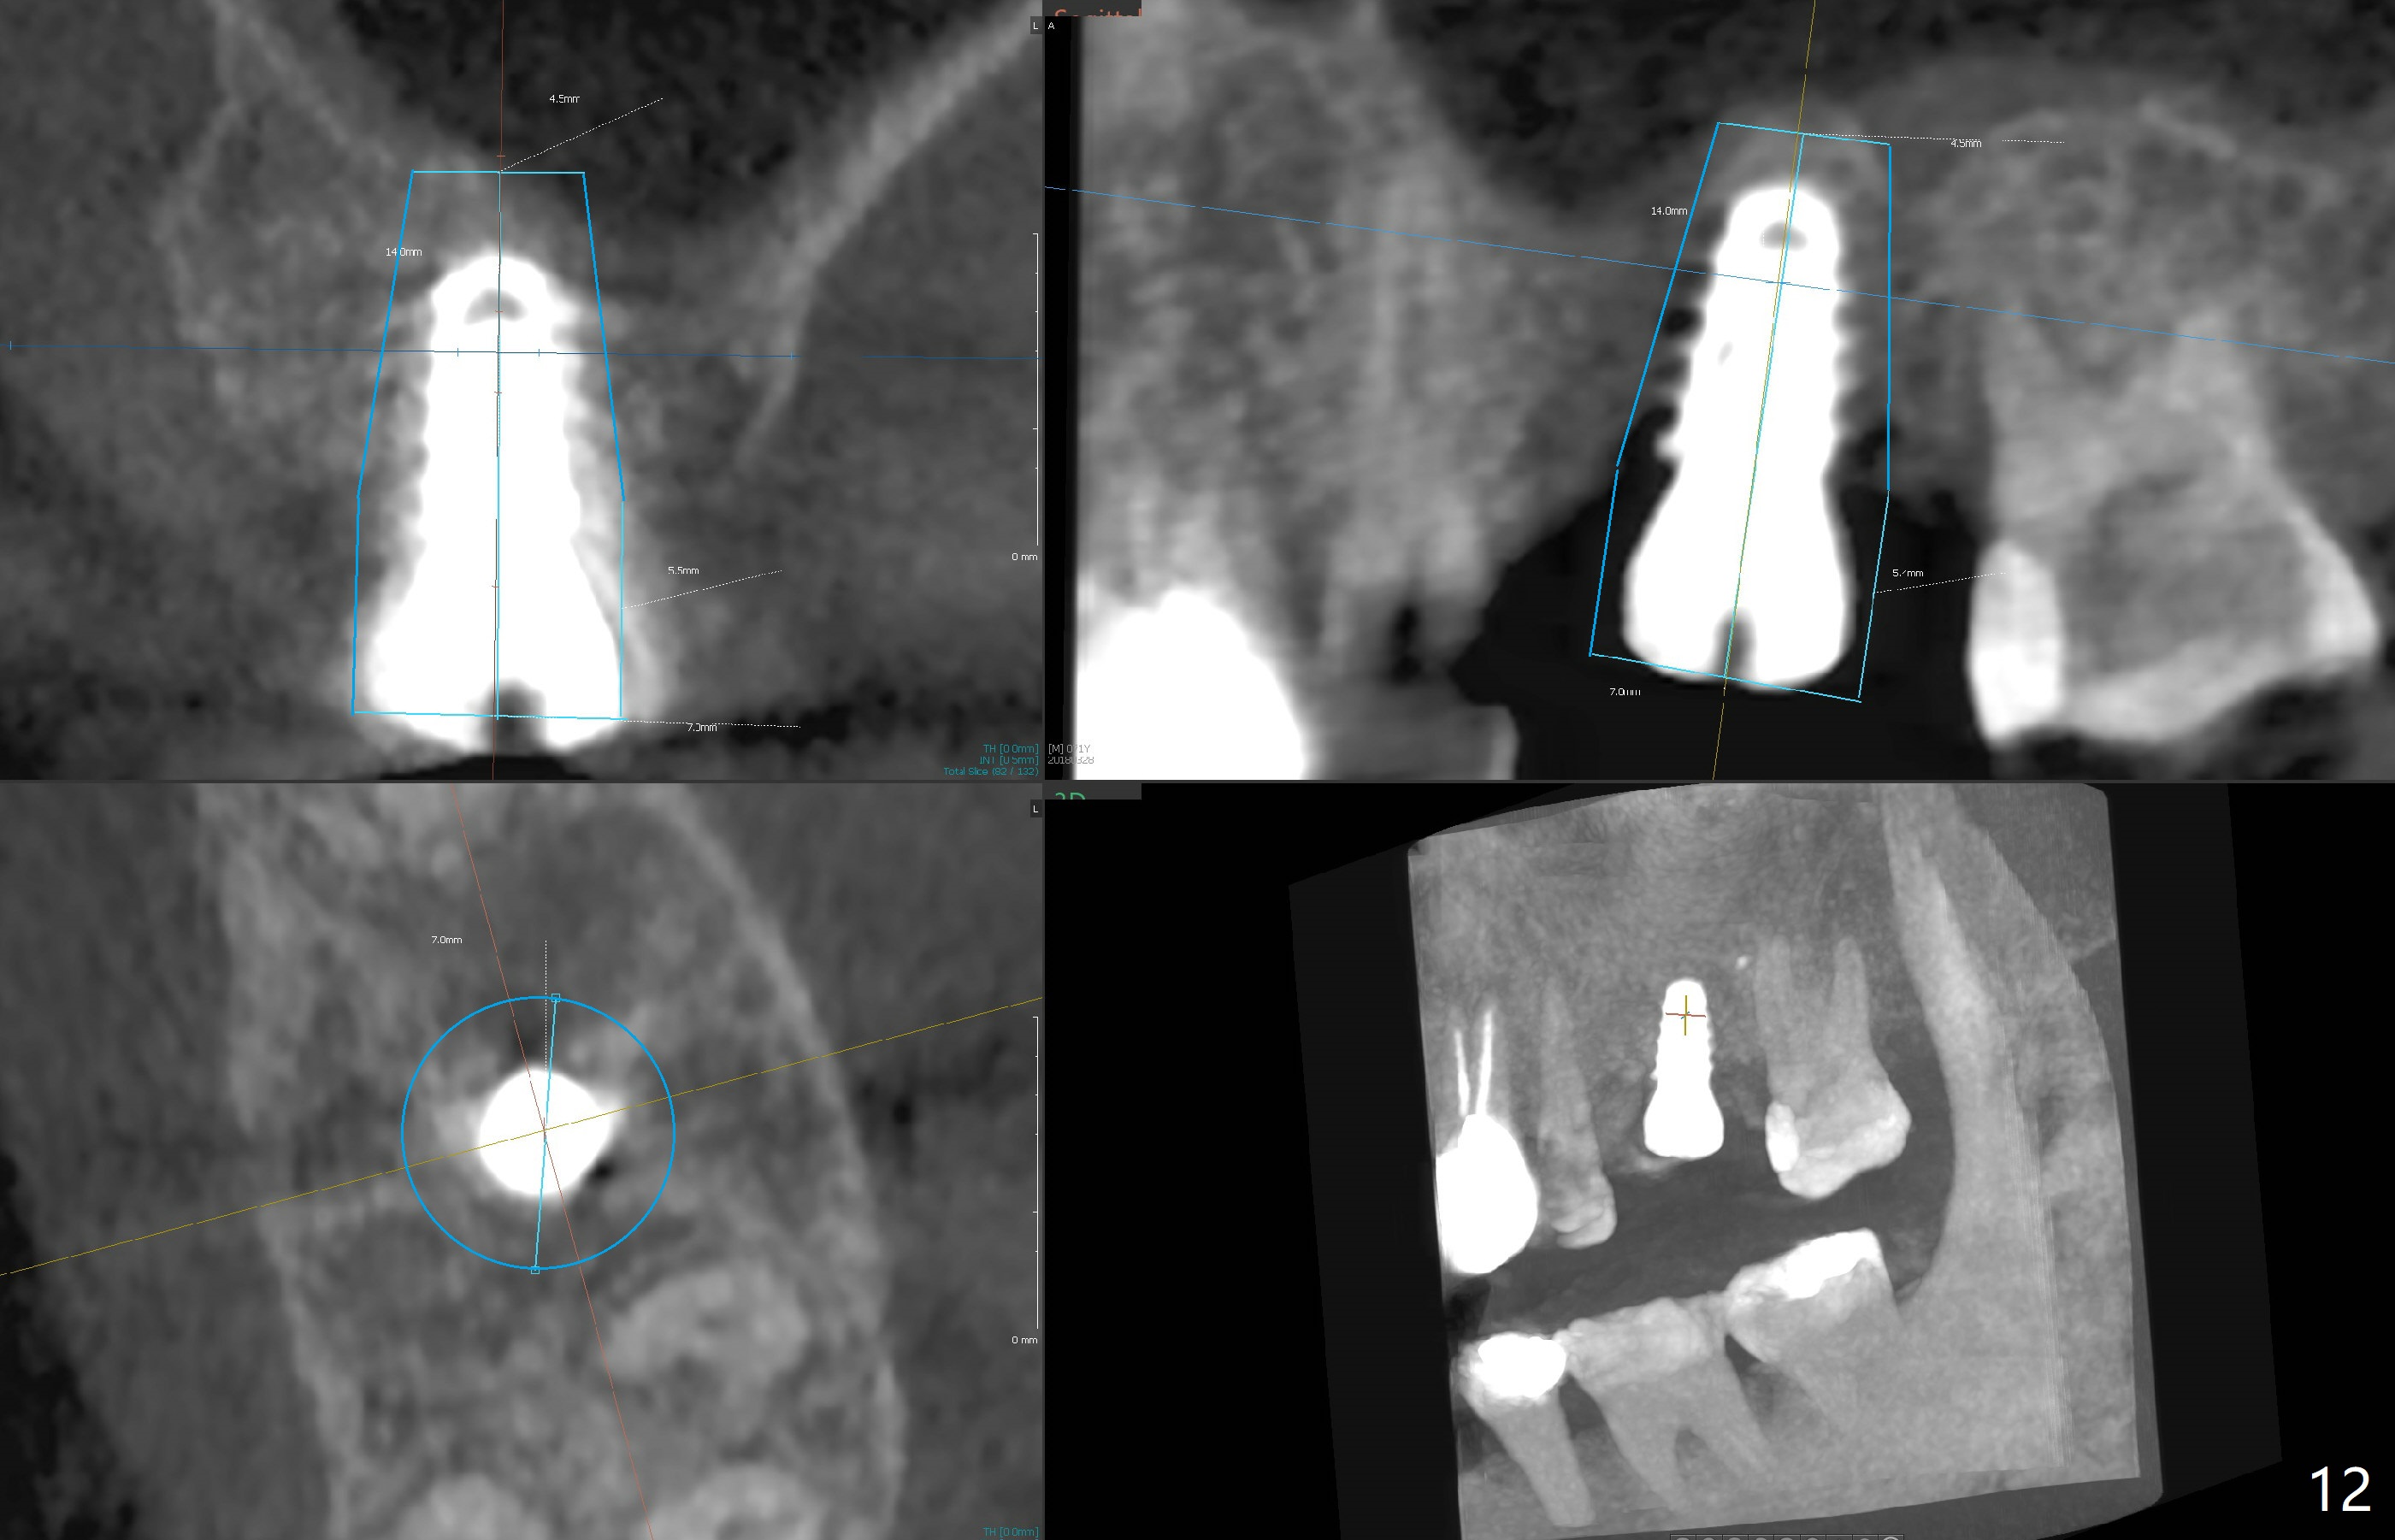

The implant is mobile 4 months postop (Fig.6).  A 6x2 mm healing abutment is placed next.  Although the implant remains mobile 6 months postop, the bone seems to have become denser around the implant (Fig.7-9).  A healing screw is placed.  When the bone height is limited (<7 mm), place a larger implant (>5.5 mm).  The implant seems to have osteointegrated 8 months postop (Fig.10).  Impression is taken following placing a 6.5x4(3) mm abutment.  The patient reports pain after cementation, which is less when the abutment screw is loose (9.5 months postop, 2 weeks post cementation).  CBCT taken after placement of a healing screw apparently shows loose bone mesial and distal to the implant (Fig.11 *).  The implant trajectory is less favorable.  It seems necessary to change to a large implant with more sold threads (Fig.12).